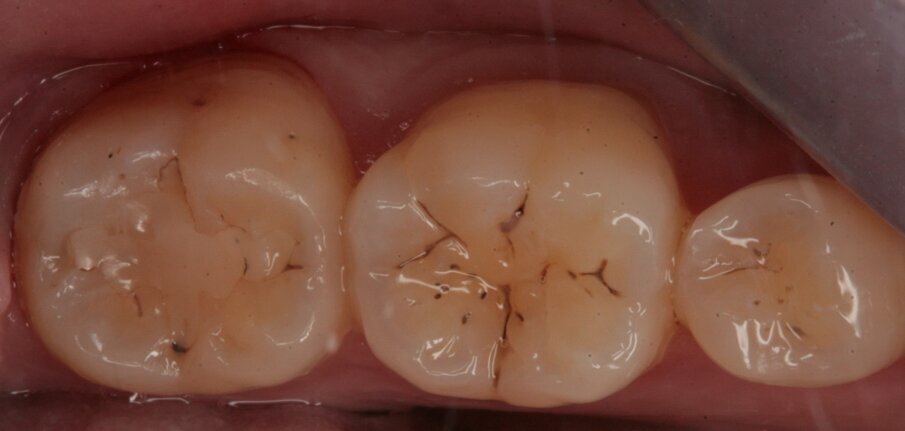

Fig. 2_Visione occlusale dell’arcata inferiore.

Fig. 13_Restauro presente sul 25.

Fig. 19_Restauro presente nell’elemento 37 e solchi interessati dal processo carioso dell’elemento 36.